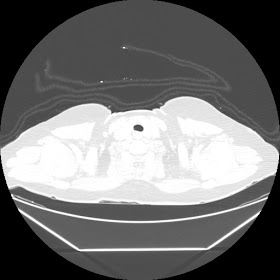

A 45 years old woman recurrent HRCT Images